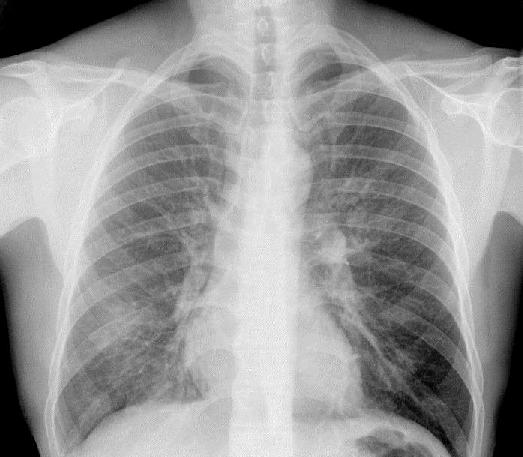

Pneumonia

Characteristics:

1. Infiltrate + "Air bronchogram"

2. Diffuse, Homogeneous

3. Location:

* Uni- og Bilateral

* Segmental or Lobar

|

The "Silhouette"

Sign = Indistinct Heart Border

Location: Middle lobe or Lingula

Example: Pneumonic infiltrate in upper segment of middle lobe (r) visible as

indistinct heart border in frontal projection

and clearly visible in lateral projection